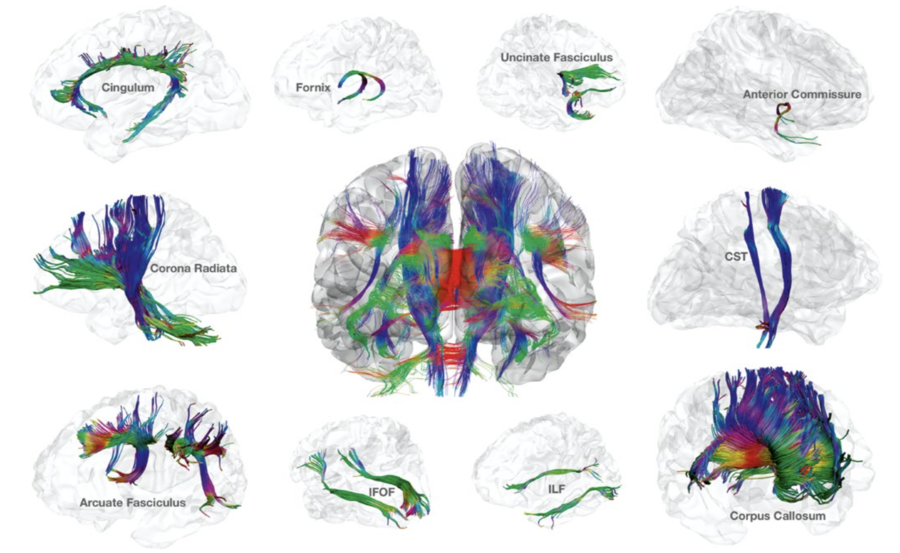

For at retningsbestemme skal DTI undersøgelsen foregå i mindst 6 forskellige retning, derefter anvendes 3D Gaussisk sandsynlighedsberegning til bestemmelse af 3x3 matriks som kaldes en diffusion tensor. En diffusion tensor er karakteriseret ved en eigen value og en eigen vector og kan man matematisk bestemme retningen af bevægelse. FA (fractional anisotropi) angiver graden af anisotropi med en FA-værdi på 0 sv.t. komplet isotopi = helt tilfældig bevægelse, til FA=1 sv.t. komplet anisotropi med udelukkende bevægelse i en retning. I en visuel fremstilling af retning vil en FA-værdig på = svarer til en kugle (en cirkel i planet) mens en FA-værdi på 1 vil svarer til en linje. FA=1 findes ikke i biologisk væv og de vil i stedet have ellipse form.

DTT fremstilles ved at tegner baner gennem eigen vektors i tilstødende voxels, man sætter typisk grænser for skarpt en "tract" mål dreje og minimums længde af de baner der skal findes.